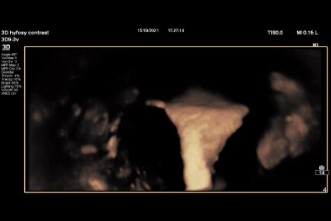

Εικόνα τρισδιάστατου υπερήχου με εύρεση ινομυώματος συγκεκριμένες μετρήσεις που είναι απαραίτητες στον προεγχειρητικό έλεγχο

Τρισδιάστατος Υπέρηχος